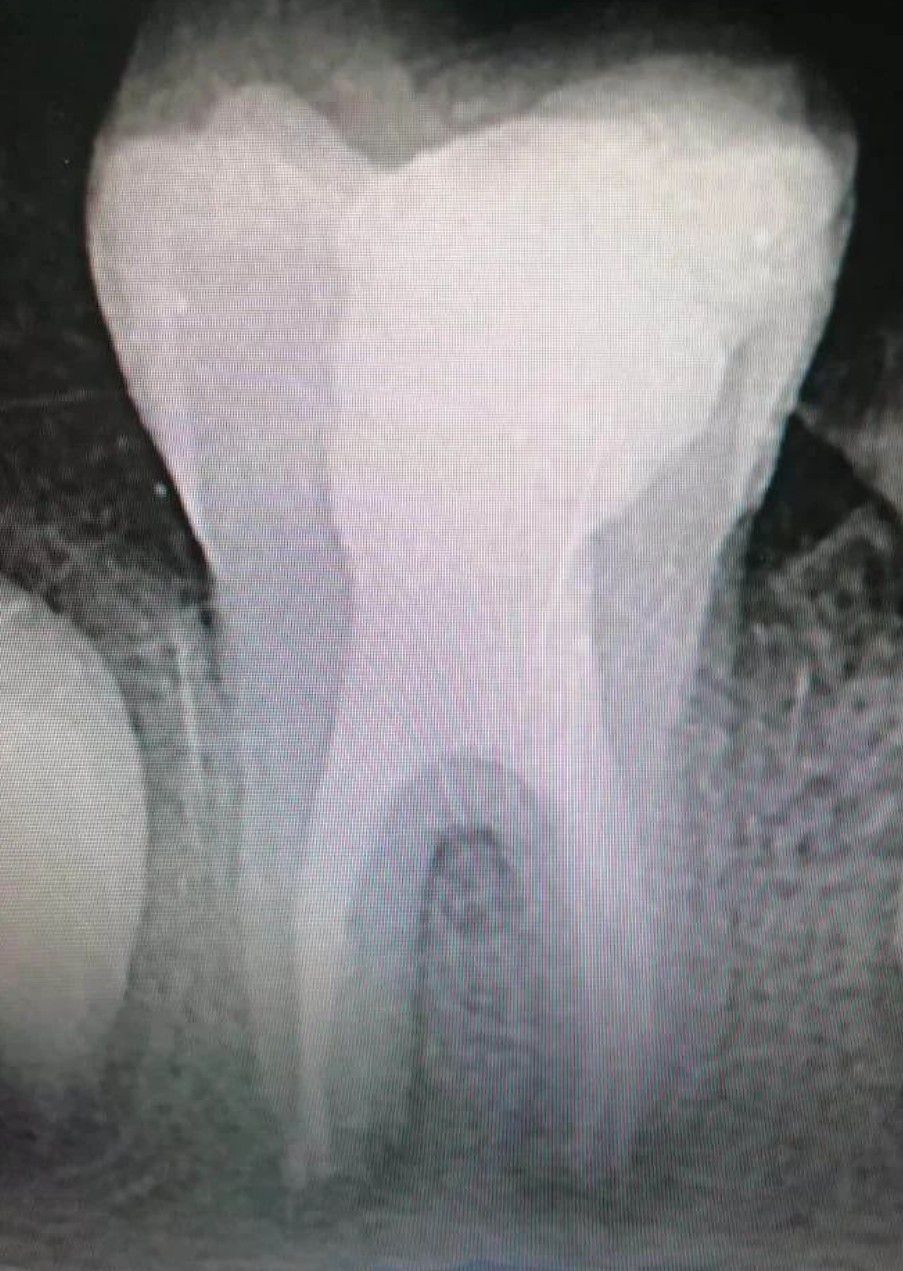

Taurodontism is a developmental disturbance of a tooth in which body is enlarged at the expense of the roots. An enlarged pulp chamber, apical displacement of the pulpal floor and lack of constriction at the cementoenamel junction are the characteristic features.